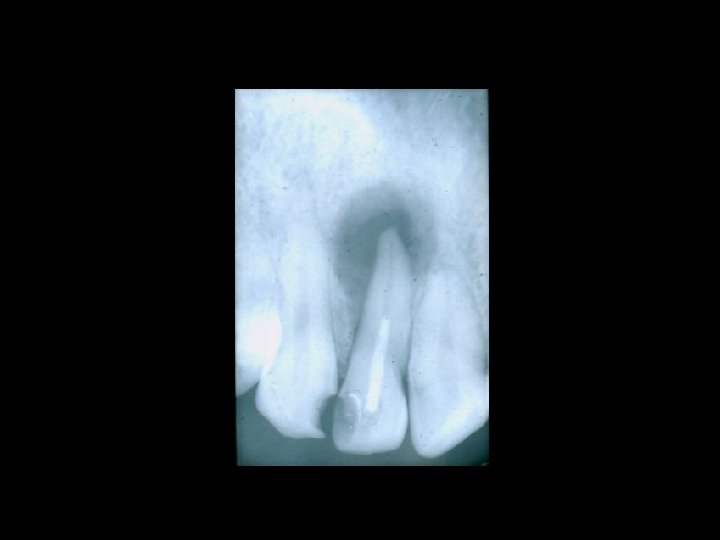

Il contenzioso PRINCIPALI AMBITI Ø Ø Ø La diagnosi La chirurgia orale La terapia conservativa Il trattamento delle anomalie dento-scheletriche La riabilitazione protesica

Responsabilità Ø Ø Ø Ø Garanzia di mezzi Garanzia di risultato Trattamento di soggetti in crescita Trattamento di soggetti al termine della crescita Comportamenti del paziente Risultato e recidiva Danni iatrogeni